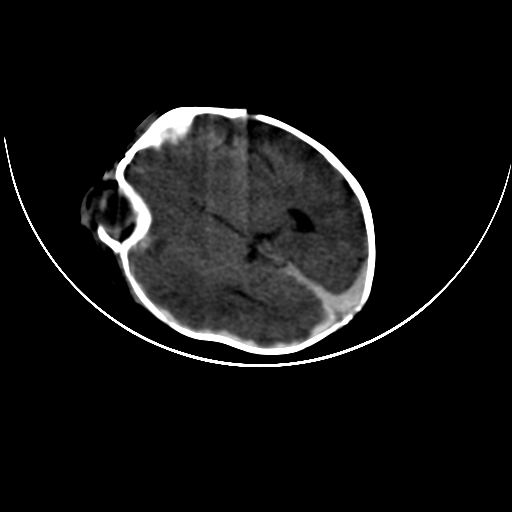

双侧硬膜下血肿并蛛网膜下腔出血。

双侧硬膜下血肿并蛛网膜下腔出血

hie 蛛网膜下腔出血,硬膜下血肿。

hie;双侧硬膜下血肿并蛛网膜下腔出血

双侧硬膜下血肿并蛛网膜下腔出血,考虑维生素k缺乏引起.

较大范围出血,应考虑维生素k缺乏引起,结合临床吧。

好像脑实质没有明显低密度影,各位大侠怎么支持hie呢?